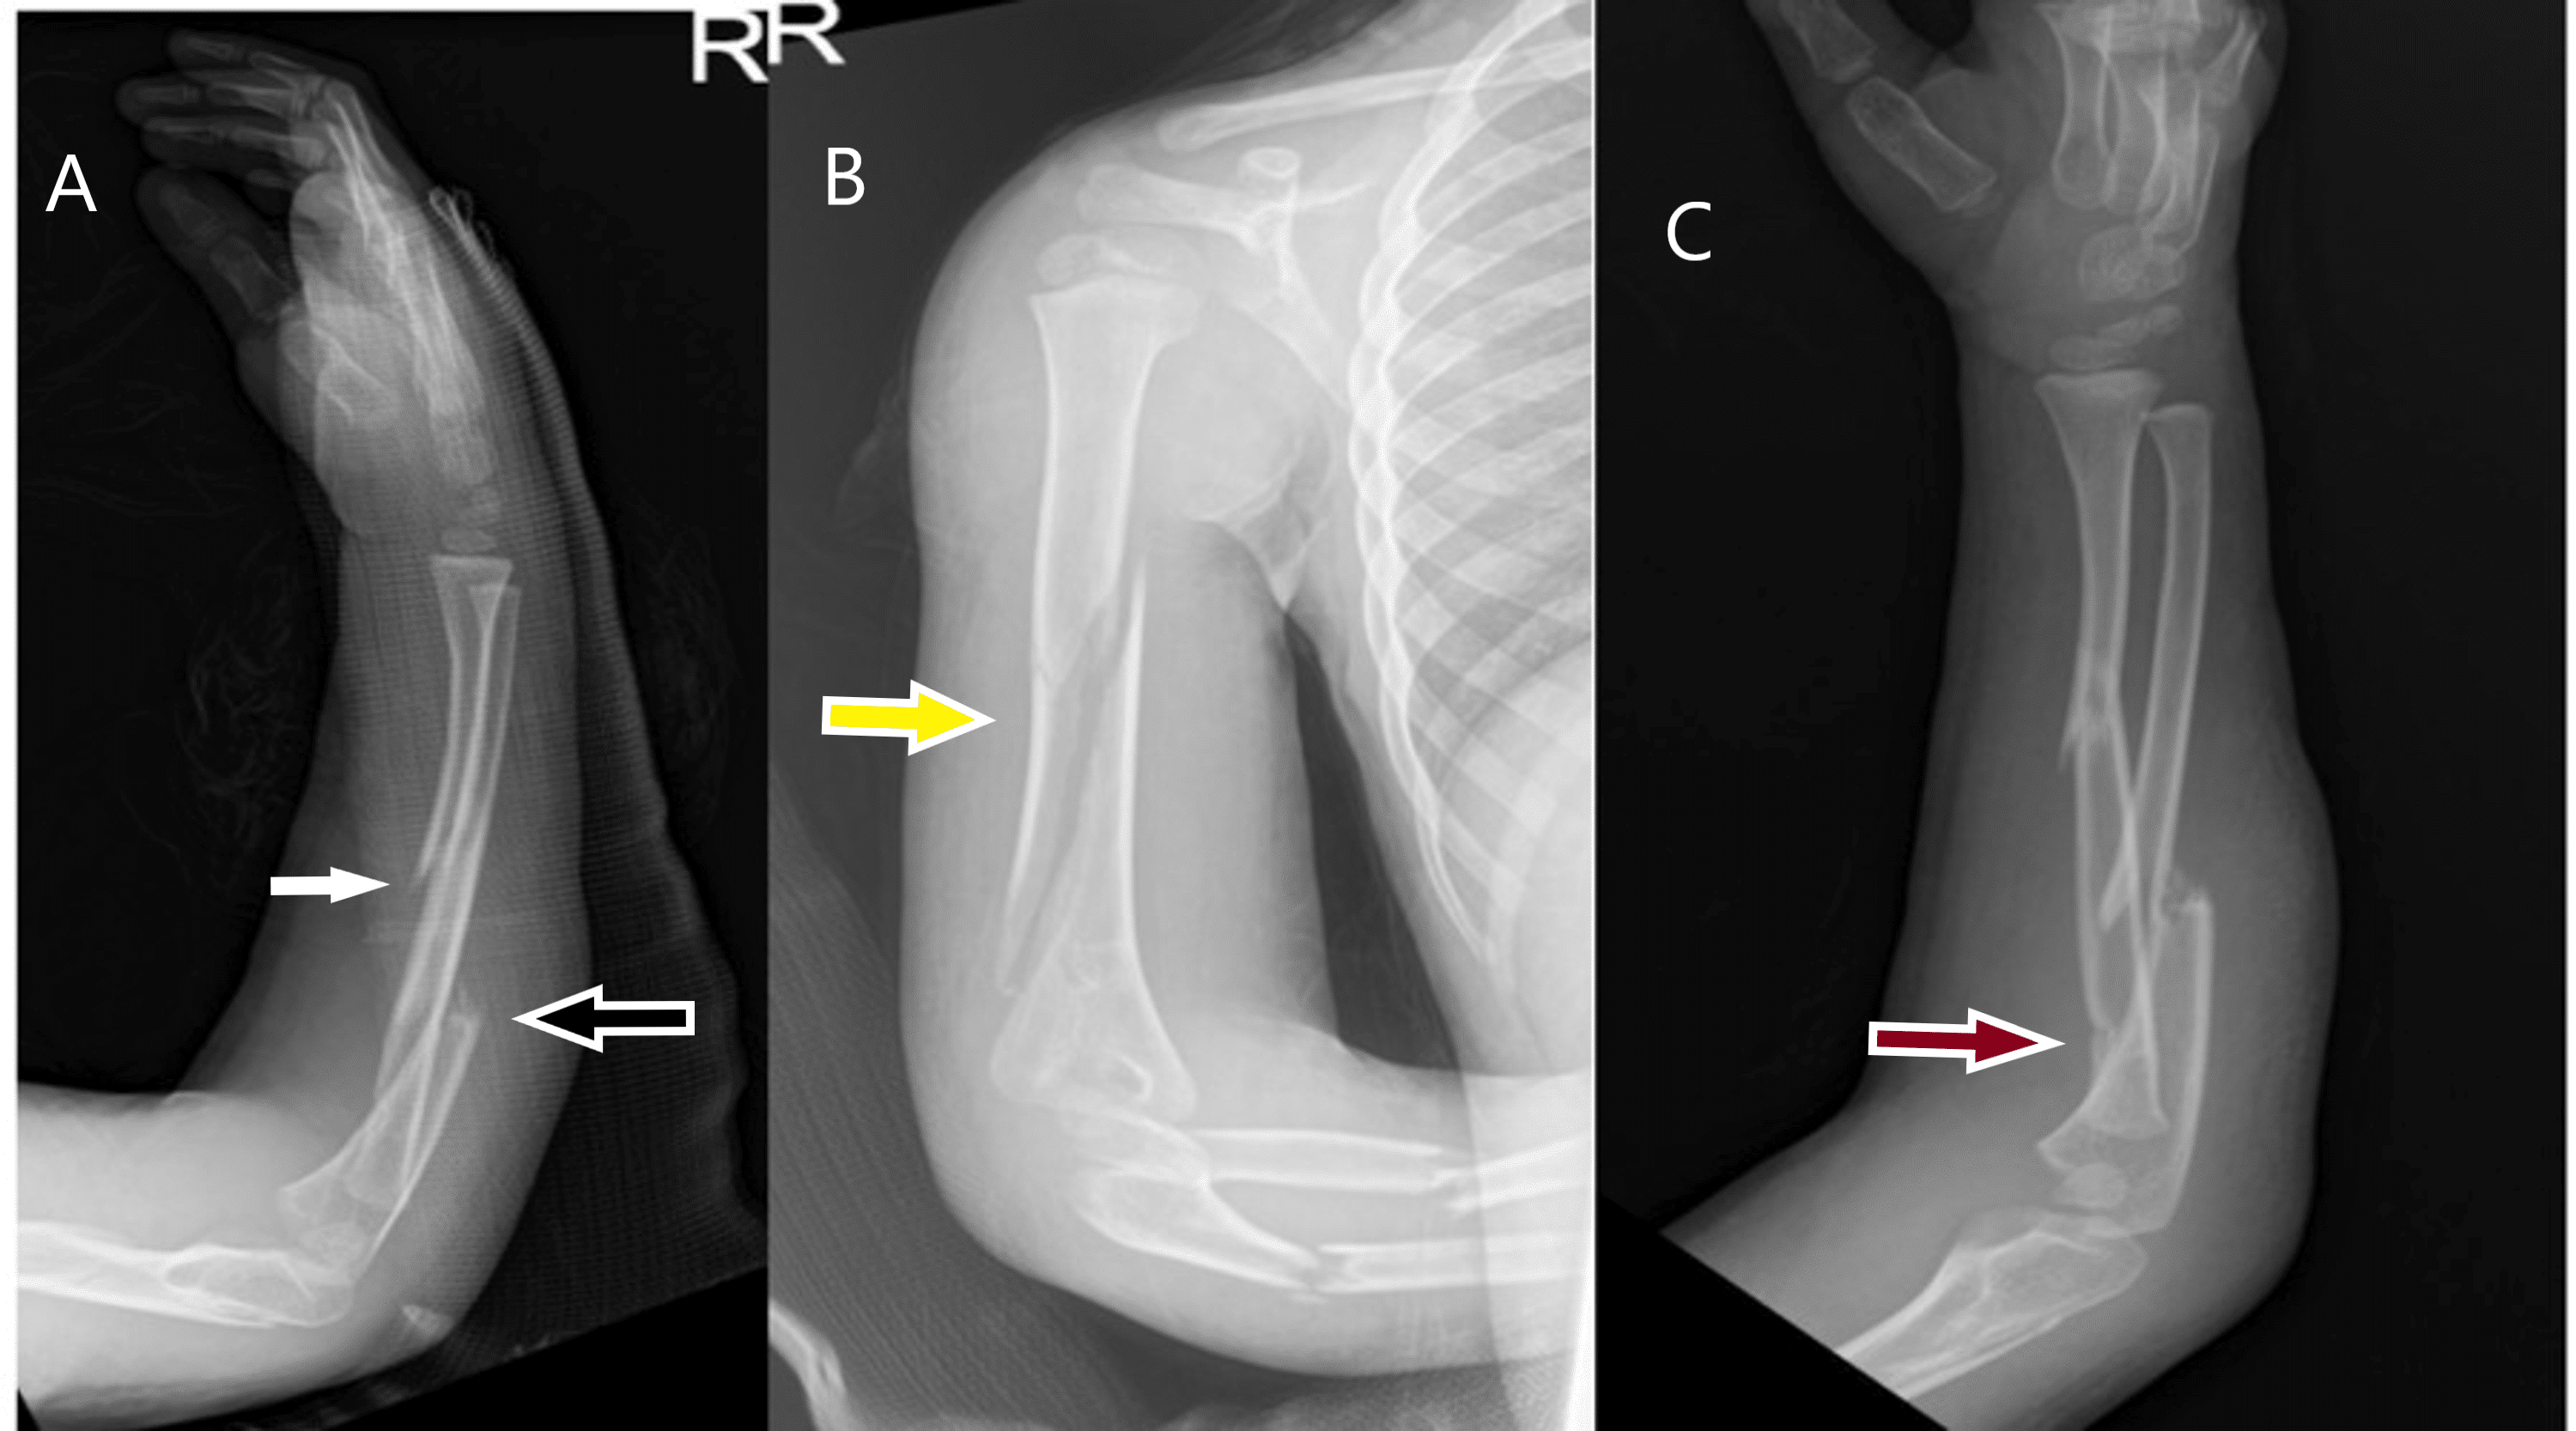

(PDF) Floating Dislocated Elbow A Variant with Articular Fracture of Floating Elbow Definition Floating elbow fractures in adults are rare and complex injuries with unpredictable outcomes. Stanitski and micheli firstly used the term “floating elbow” to describe ipsilateral humerus fracture combined with forearm. The present study was designed to. The term floating elbow was first introduced by stanitski and micheli to describe an injury pattern in children involving concomitant. The current knowledge regarding. Floating Elbow Definition.